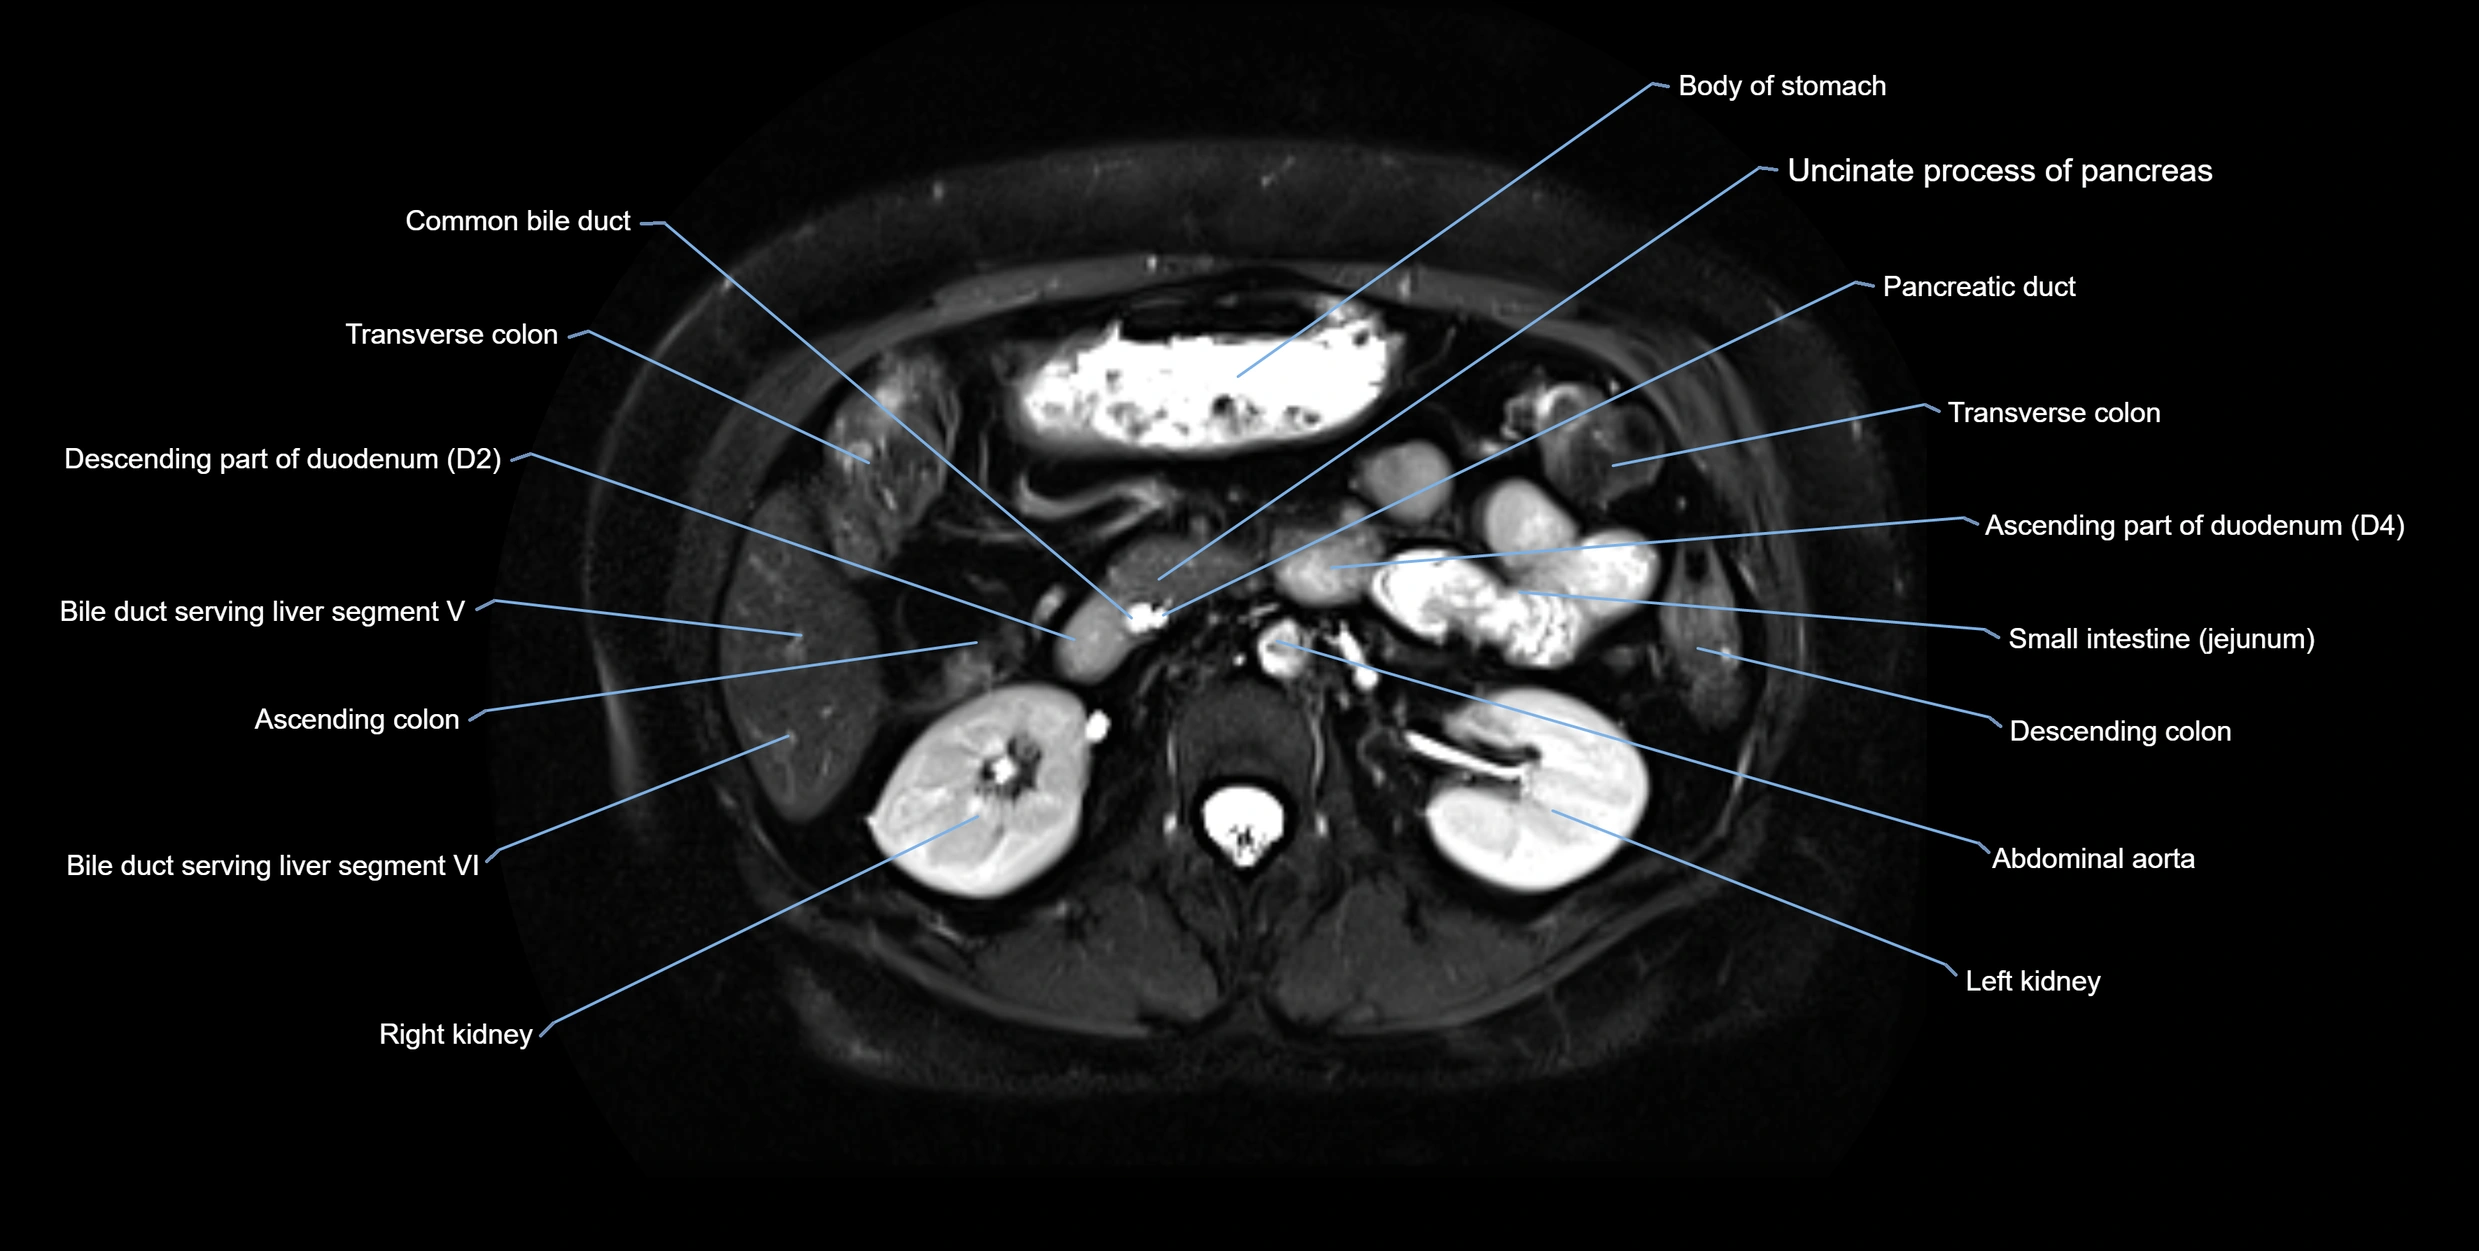

MRI Appearance

T2-weighted images:

T2 Fat-Saturated HASTE (single-shot):

• Excellent for rapid evaluation of duct patency